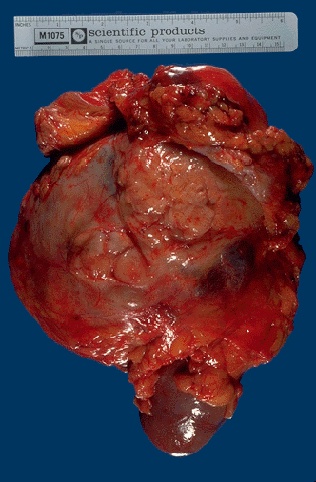

This renal cell carcinoma is very large, as indicated by the 15 cm ruler. A portion of normal kidney protrudes at the lower center. This patient was a physician himself and just didn't have any early symptoms.